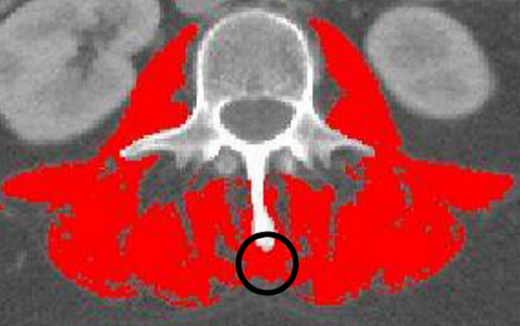

Be careful not to analyze organs that might be touching the skeletal muscle such as intestines, liver, or kidneys as muscle.